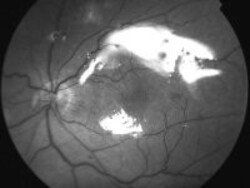

Imágenes

Figura 2. Desprendimiento de retina inferior y su imagen luego de vitrectomía y utilización de gas expansible C3F8 al 15% con láser inferior.